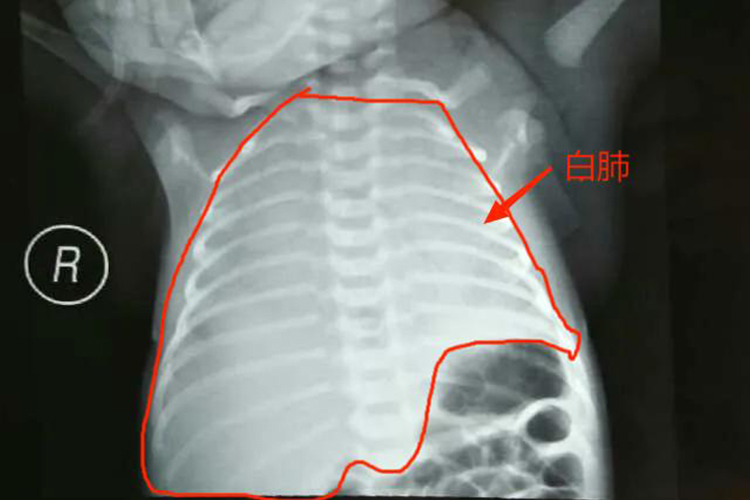

白肺病是指肺部影像学检查中,患者双肺出现大范围白色影像区的病变,表面肺部有大量的渗出物,且累及多个肺叶。此病可能是多种原因导致,症状不看发热、咳嗽等。

- 白肺病的诊断需要综合病史、体格检查、实验室检查和影像学检查等临床资料,其中病原学检查是诊断白肺病因的主要辅助检查。